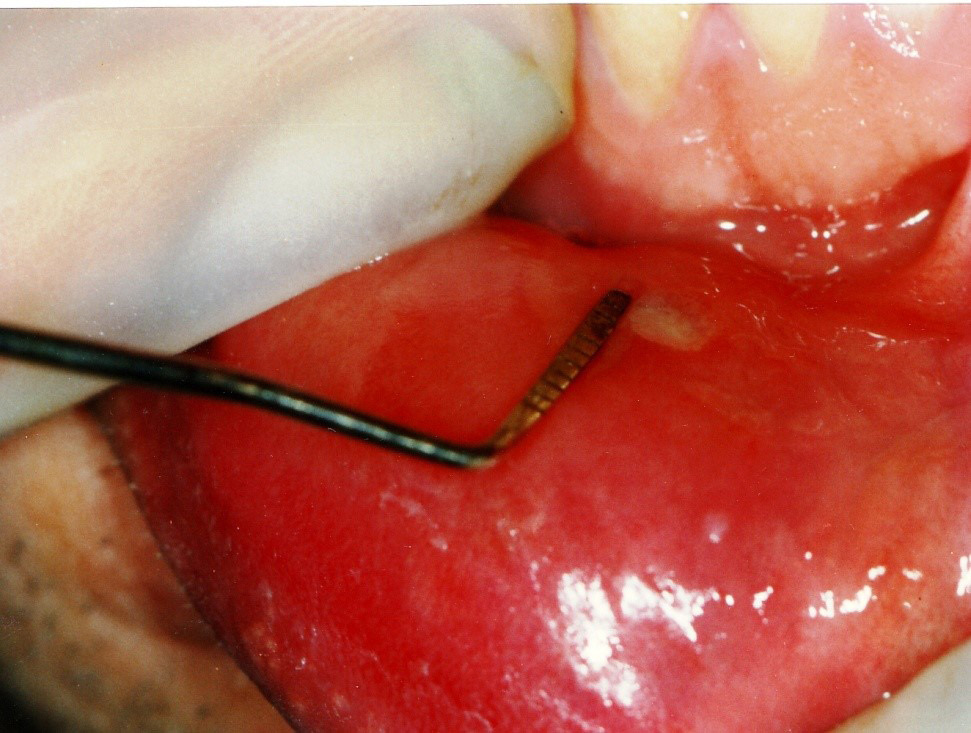

For all groups, the PBM procedure was performed on the 1st, 2nd and 3rd day. The patients were asked for recall visits on the 7th, 14th, 30th, and 60th day of treatment (Figure 3). Clinical presentations, including pain and the lesion size, were recorded at each visit. A periodontal probe was used to measure the lesion size (Figure 4). Pain intensity and duration, the recurrence intervals of both pain and lesions, and the lesion diameter were also recorded at each visit based on the consented study scales scoring from 0 to 2.